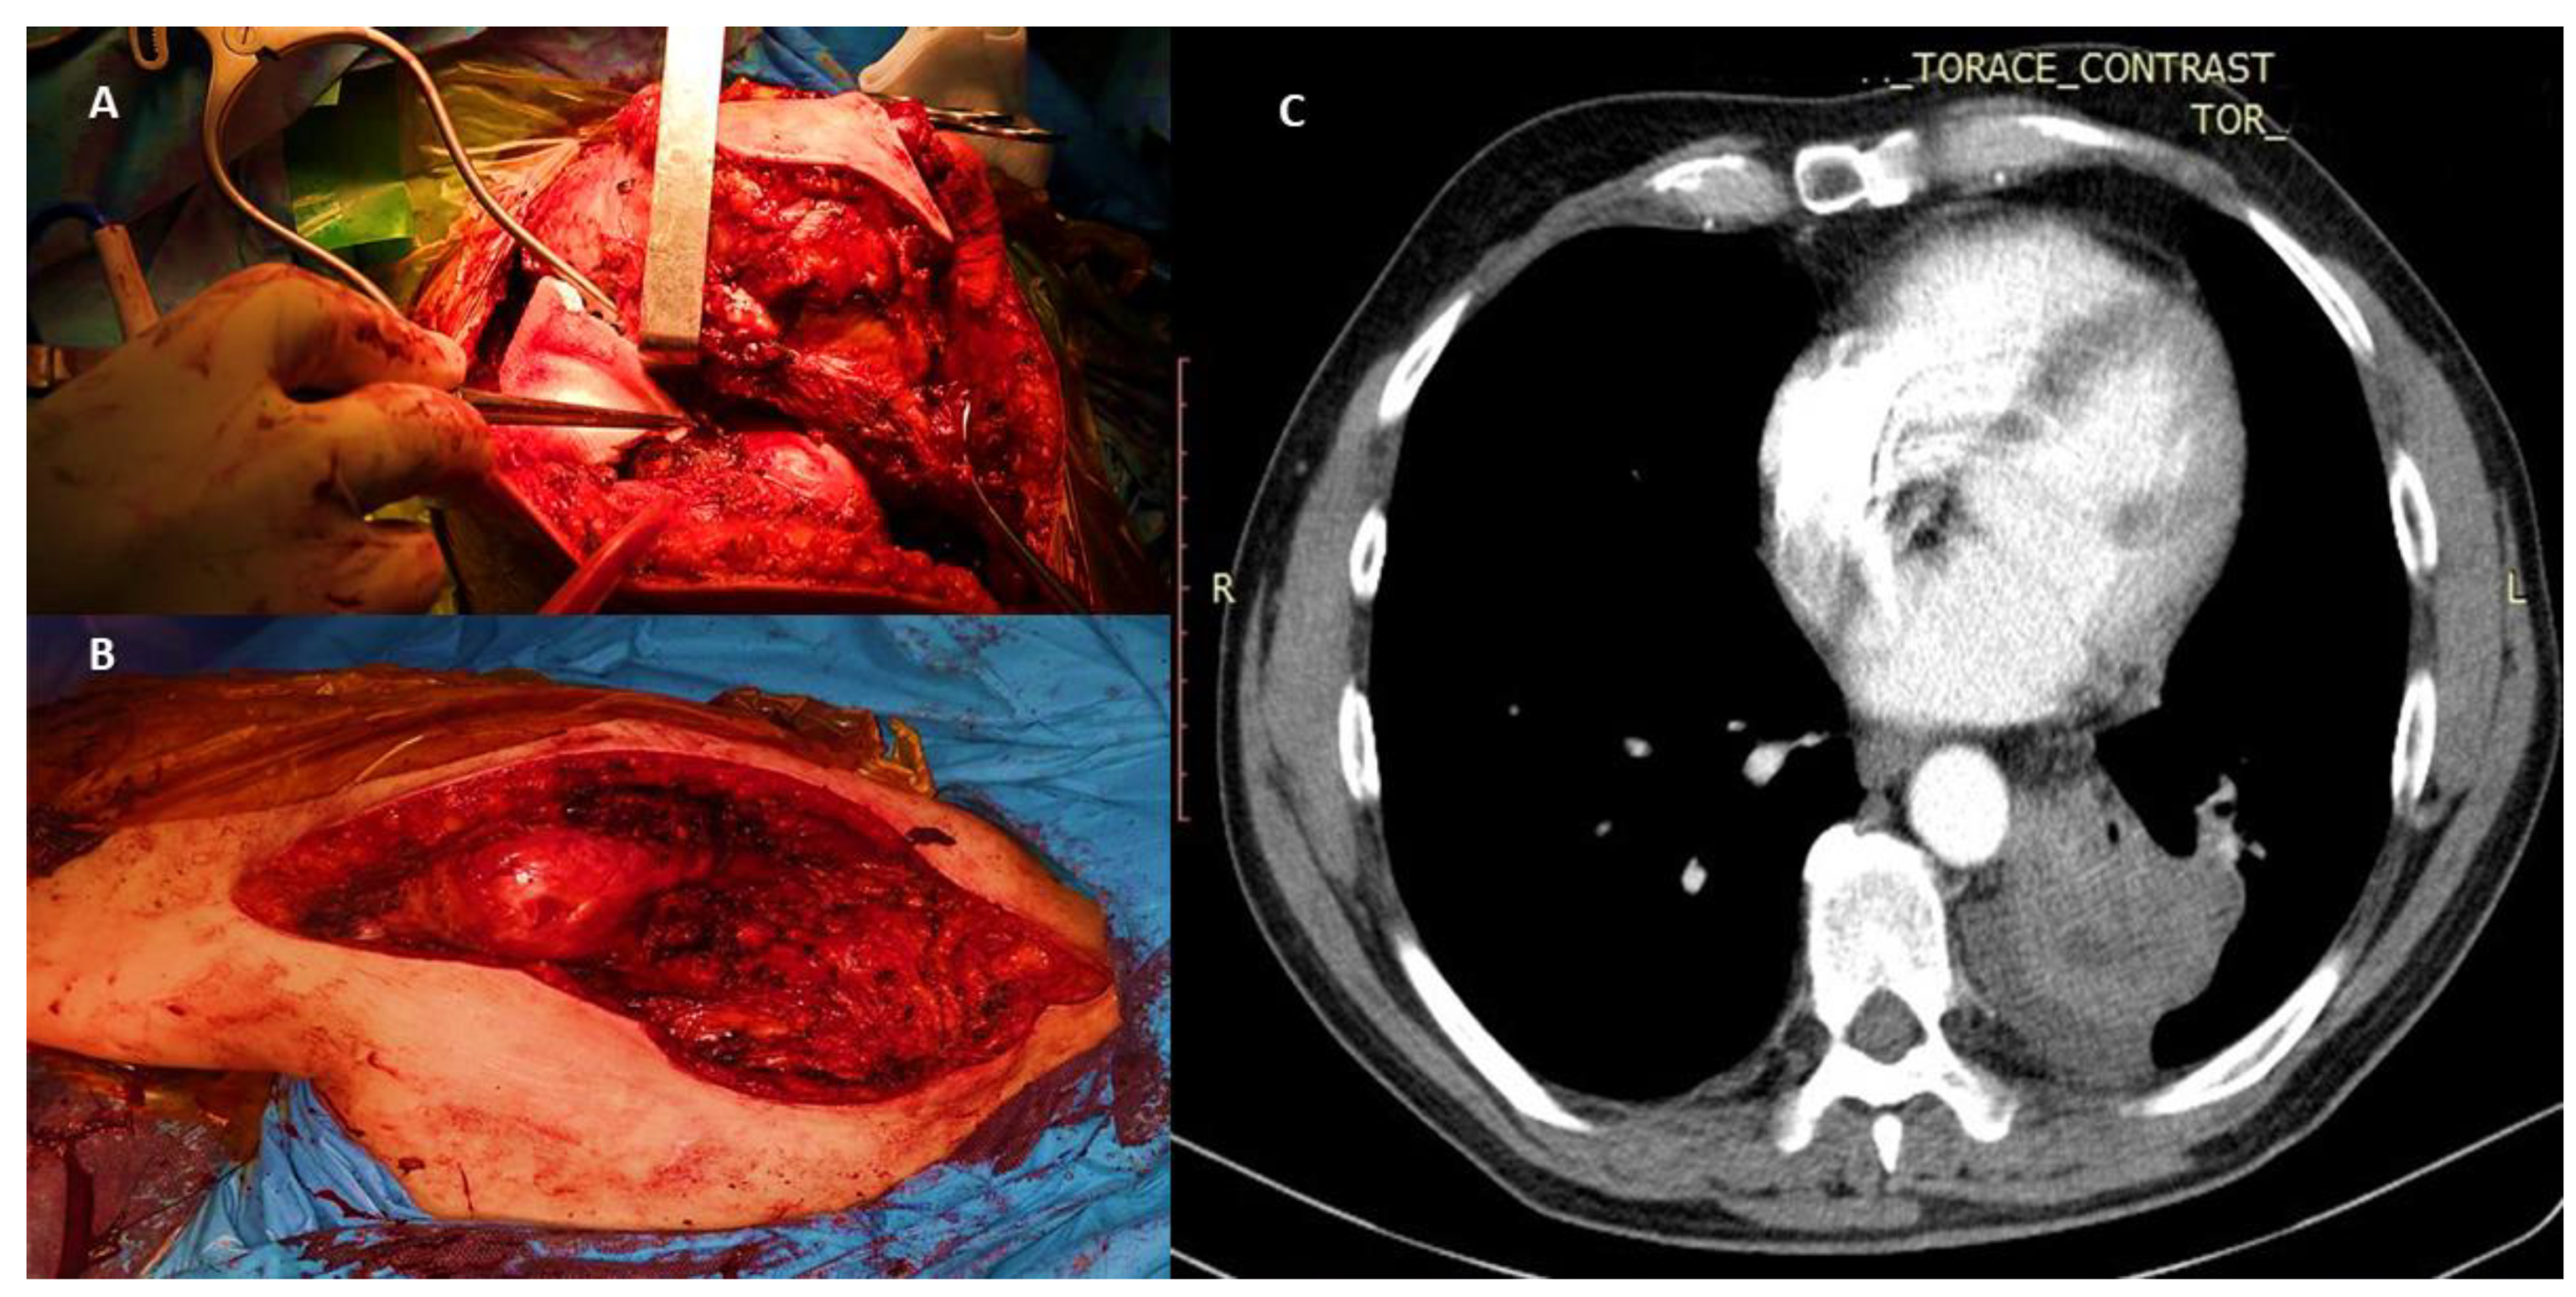

5.1. Surgical Treatment Indications and Techniques Used in Single Bone Metastases Associated with Lung Cancer

5.2. Resection and Reconstruction of Solitary Bone Lesions in Lung Cancer

5.3. Treatment of Complete or Impending Fractures in Unique Bone Metastasis following Lung Cancer—Resection Followed by Intramedullary Nails and Acrylic Bone Cement